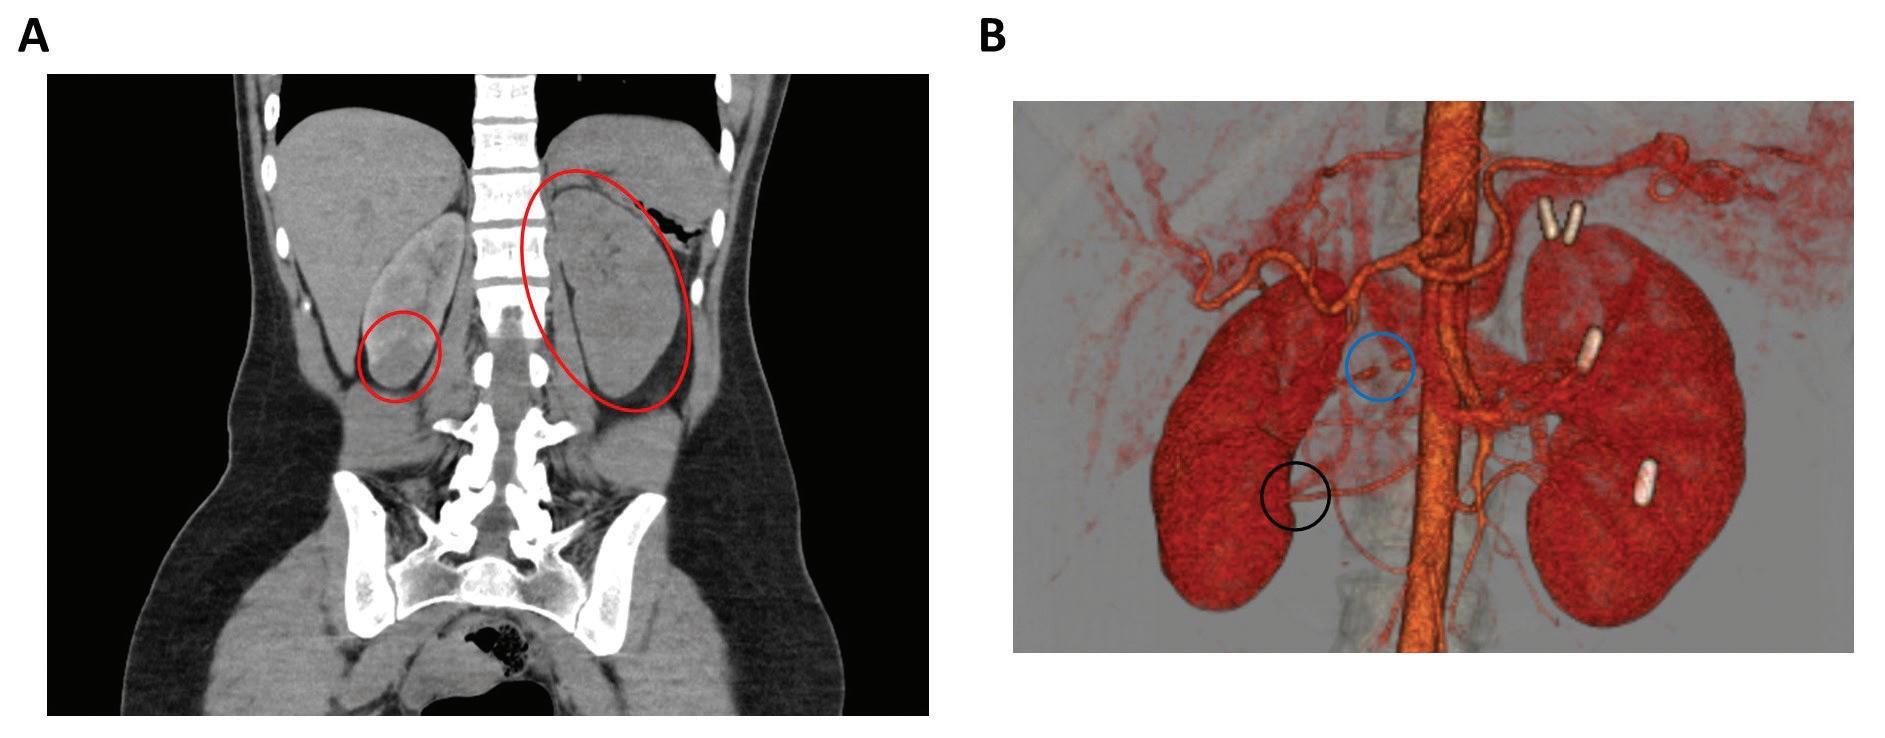

115 A Presentation of PRES with Rapid Cortical Enhancement Caused by Hypertension Secondary to Structural Renal Abnormalities

Joshua Quach, Rachel Gifeisman, and Suman Kaza